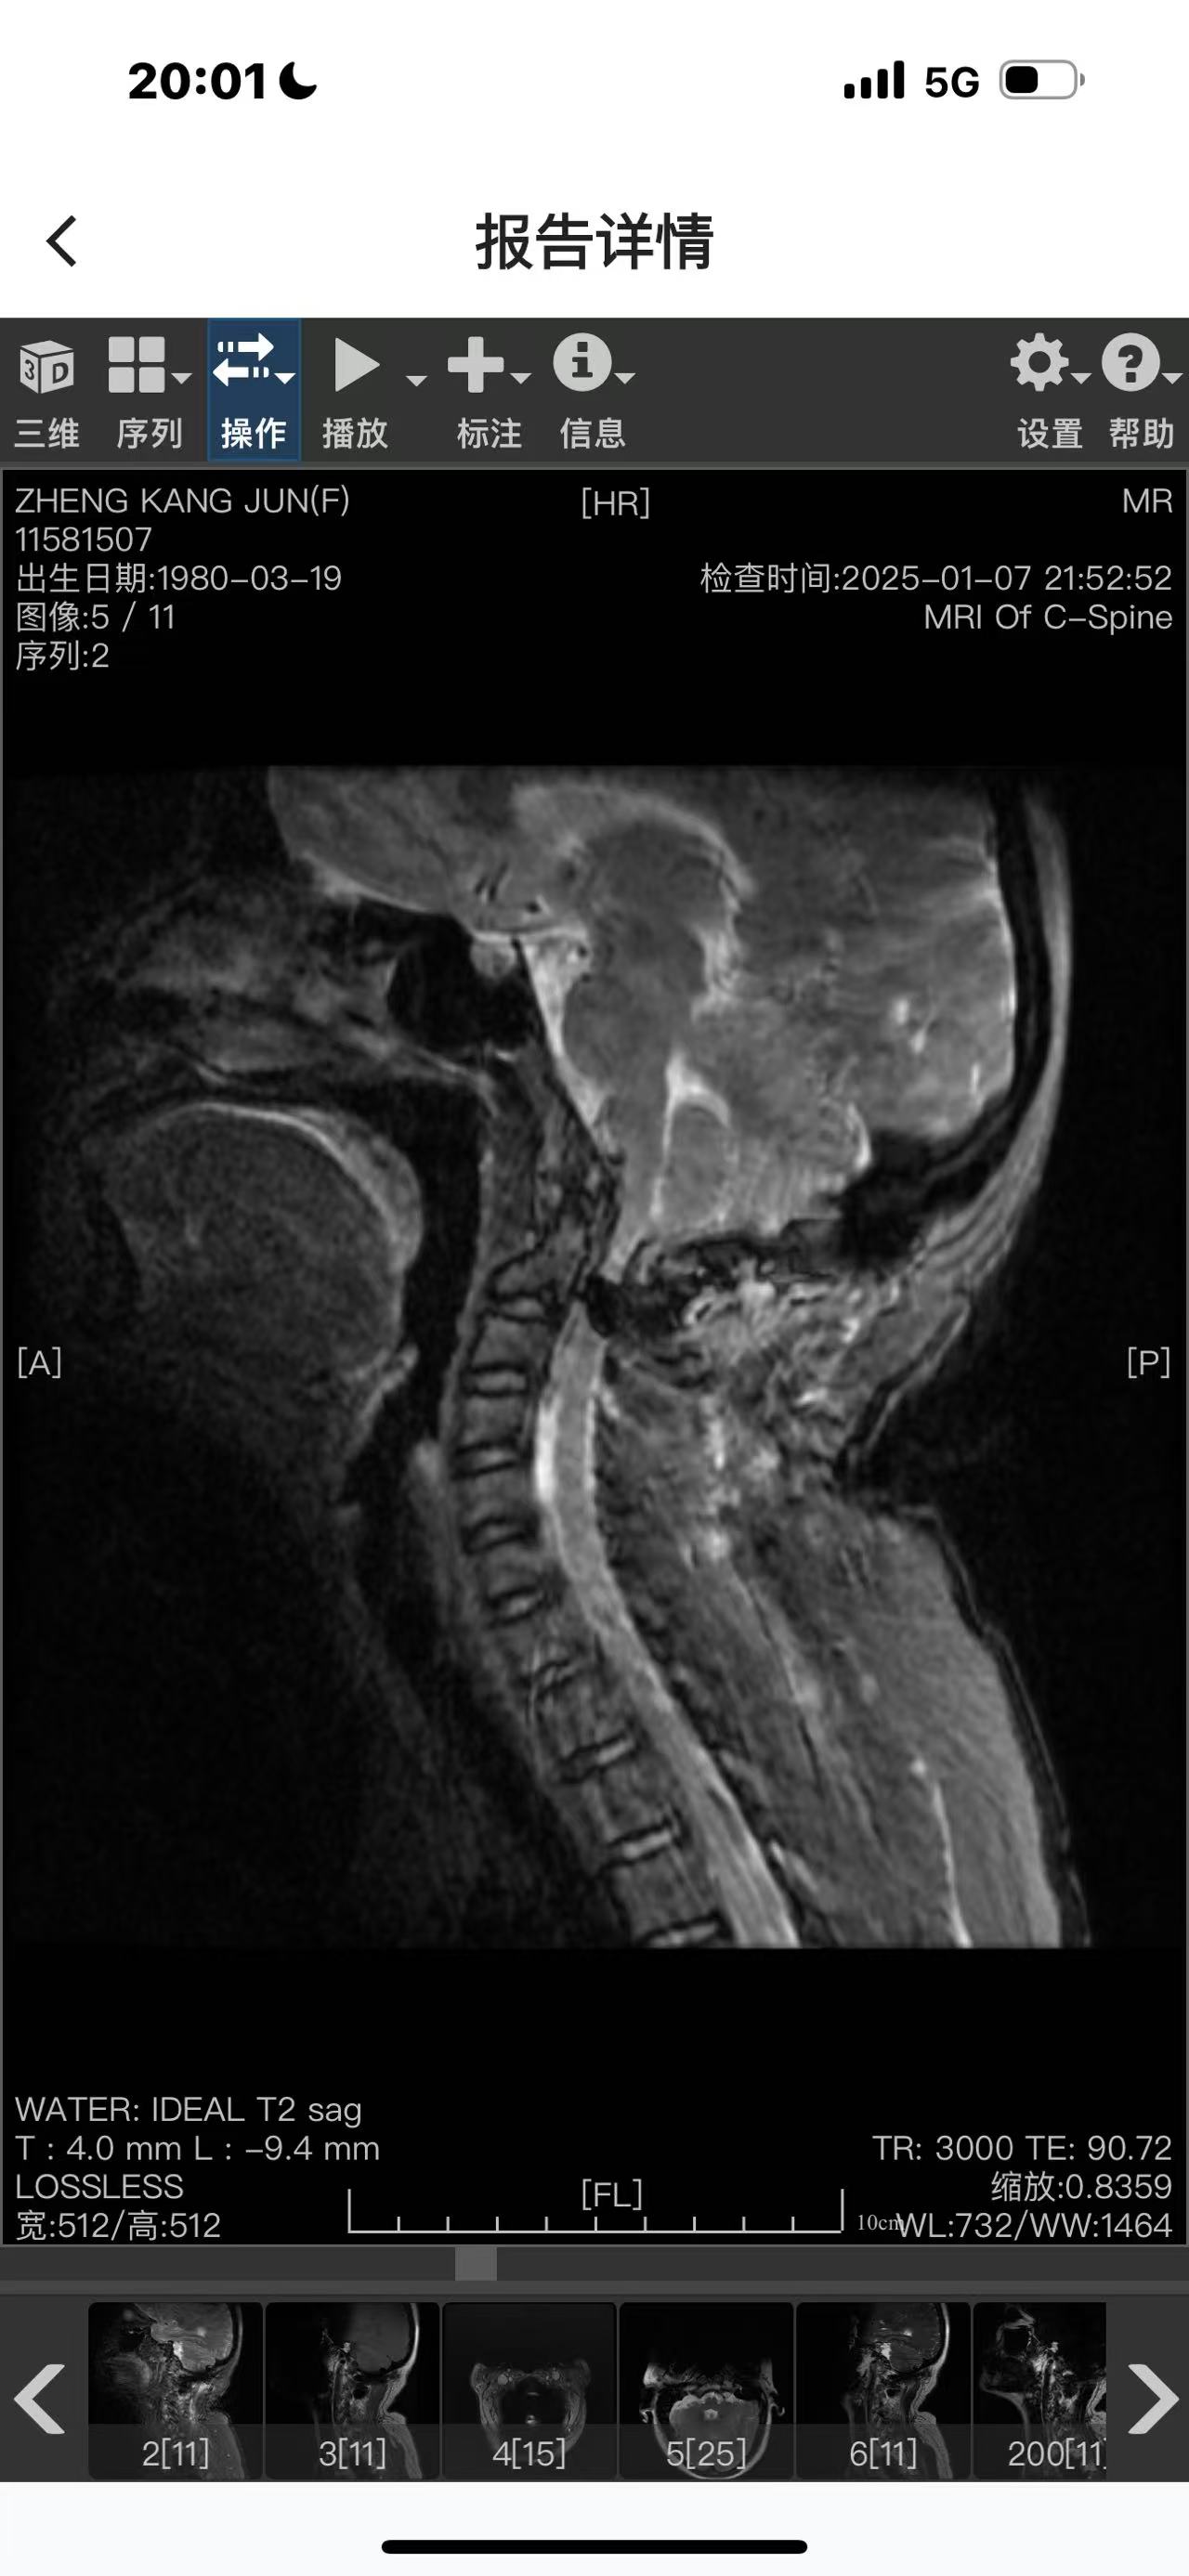

• 诊断:寰枢椎脱位

• 影像:

二次手术#

• 日期:2024.12.30

• 医院:人民医院

• 主刀:王超

• 术后状况:

• 术后影像: